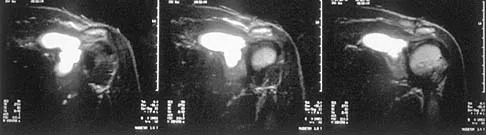

A 50-year-old man with no history of trauma reports new-onset back pain after doing some yard work the previous day. He reports pain radiating down his leg posteriorly and into the first dorsal web space of his foot. MRI scans are shown in Figures 3a through 3c. What nerve root is affected?